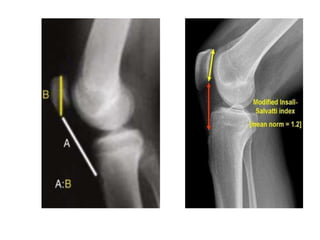

 A lateral view with the knee in slight flexion may show a high-riding

patella

• The Insall-Salvati ratio or index is the ratio of the patella

tendon length (TL) to the length of the patella (PL).

• - Insall-Salvati method for determining patella alta/baja

• - Normal (T/P) = 0.80 - 1.2

• - Patella Infera/Baja < .80 possible Quad tendon rupture

• - Patella Alta > 1.2 possible Patella tendon ruptur

Radiology :  mayshow patella in a lower position than normal, use contralateral patella for comparison  Partial tear - in these patients, MRI may delineate the extent of injury.

• The Insall-Salvatiratio or index is the ratio of the patella tendon length (TL) to the length of the patella (PL). • - Insall-Salvati method for determining patella alta/baja • - Normal (T/P) = 0.80 - 1.2 • - Patella Infera/Baja < .80 possible Quad tendon rupture • - Patella Alta > 1.2 possible Patella tendon ruptur